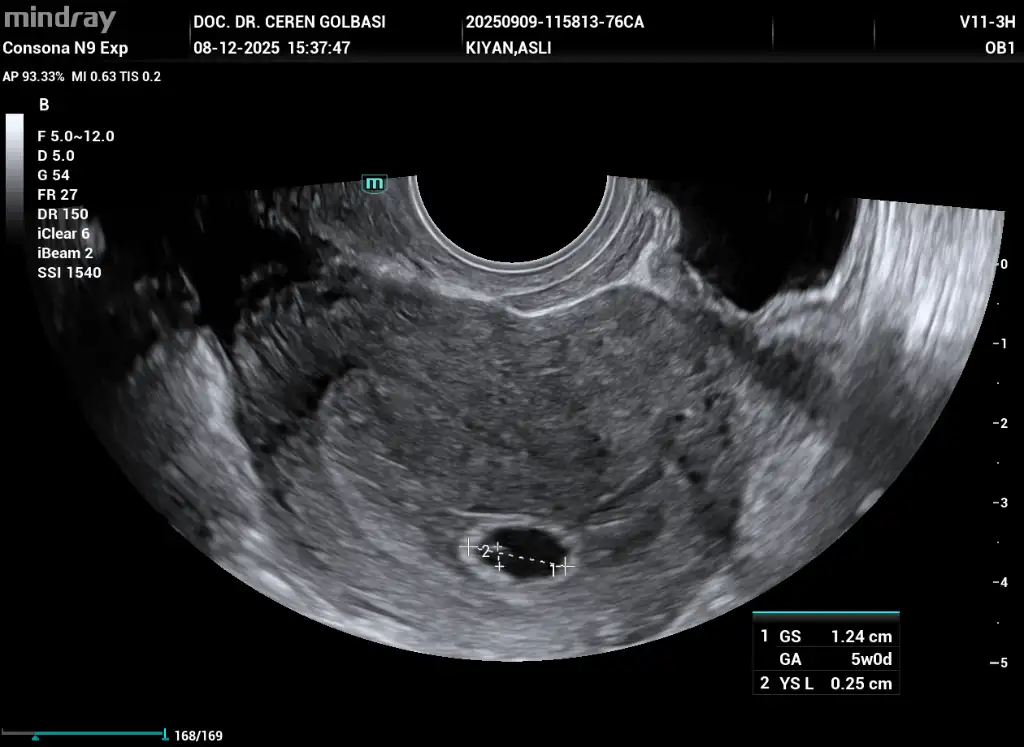

Bugün doktora gittim son adet tarihim 26 ekimdi bebeği göremedik 5+4 olarak söyledi şu anki durumumu benimle aynı olan var mı acaba birde kistim varmış çok ağrı yapıyor kist geçer değil mi

• _QRCodeSendTask_20251208154216_QR_1_202512081538310103OB.webp

_QRCodeSendTask_20251208154216_QR_1_202512081538310103OB.webp

31,8 KB · Görüntüleme: 3